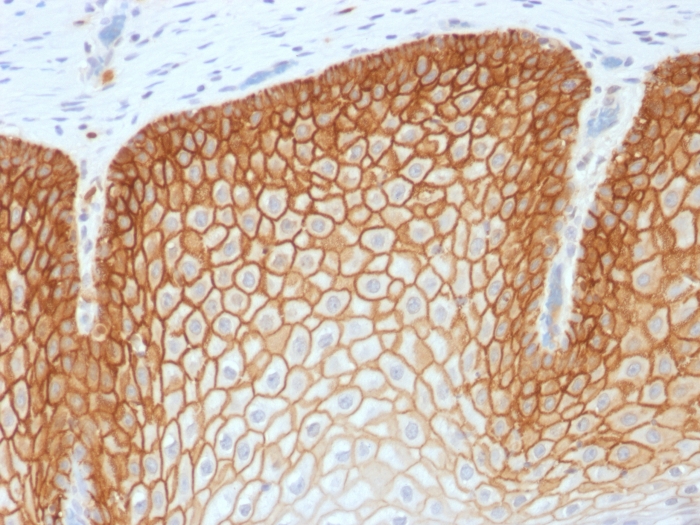

IHC-P analysis of human cervical squamous cell carcinoma tissue using GTX34521 CD44v4 antibody [CD44v4/1700R].

This antibody recognizes an epitope encoded by exon v4 on the variant portion of human CD44.

CD44v4 antibody [CD44v4/1700R]